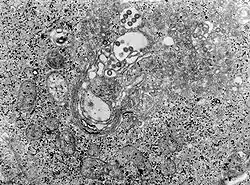

TEM micrograph of tissue infected with Rift Valley fever virus